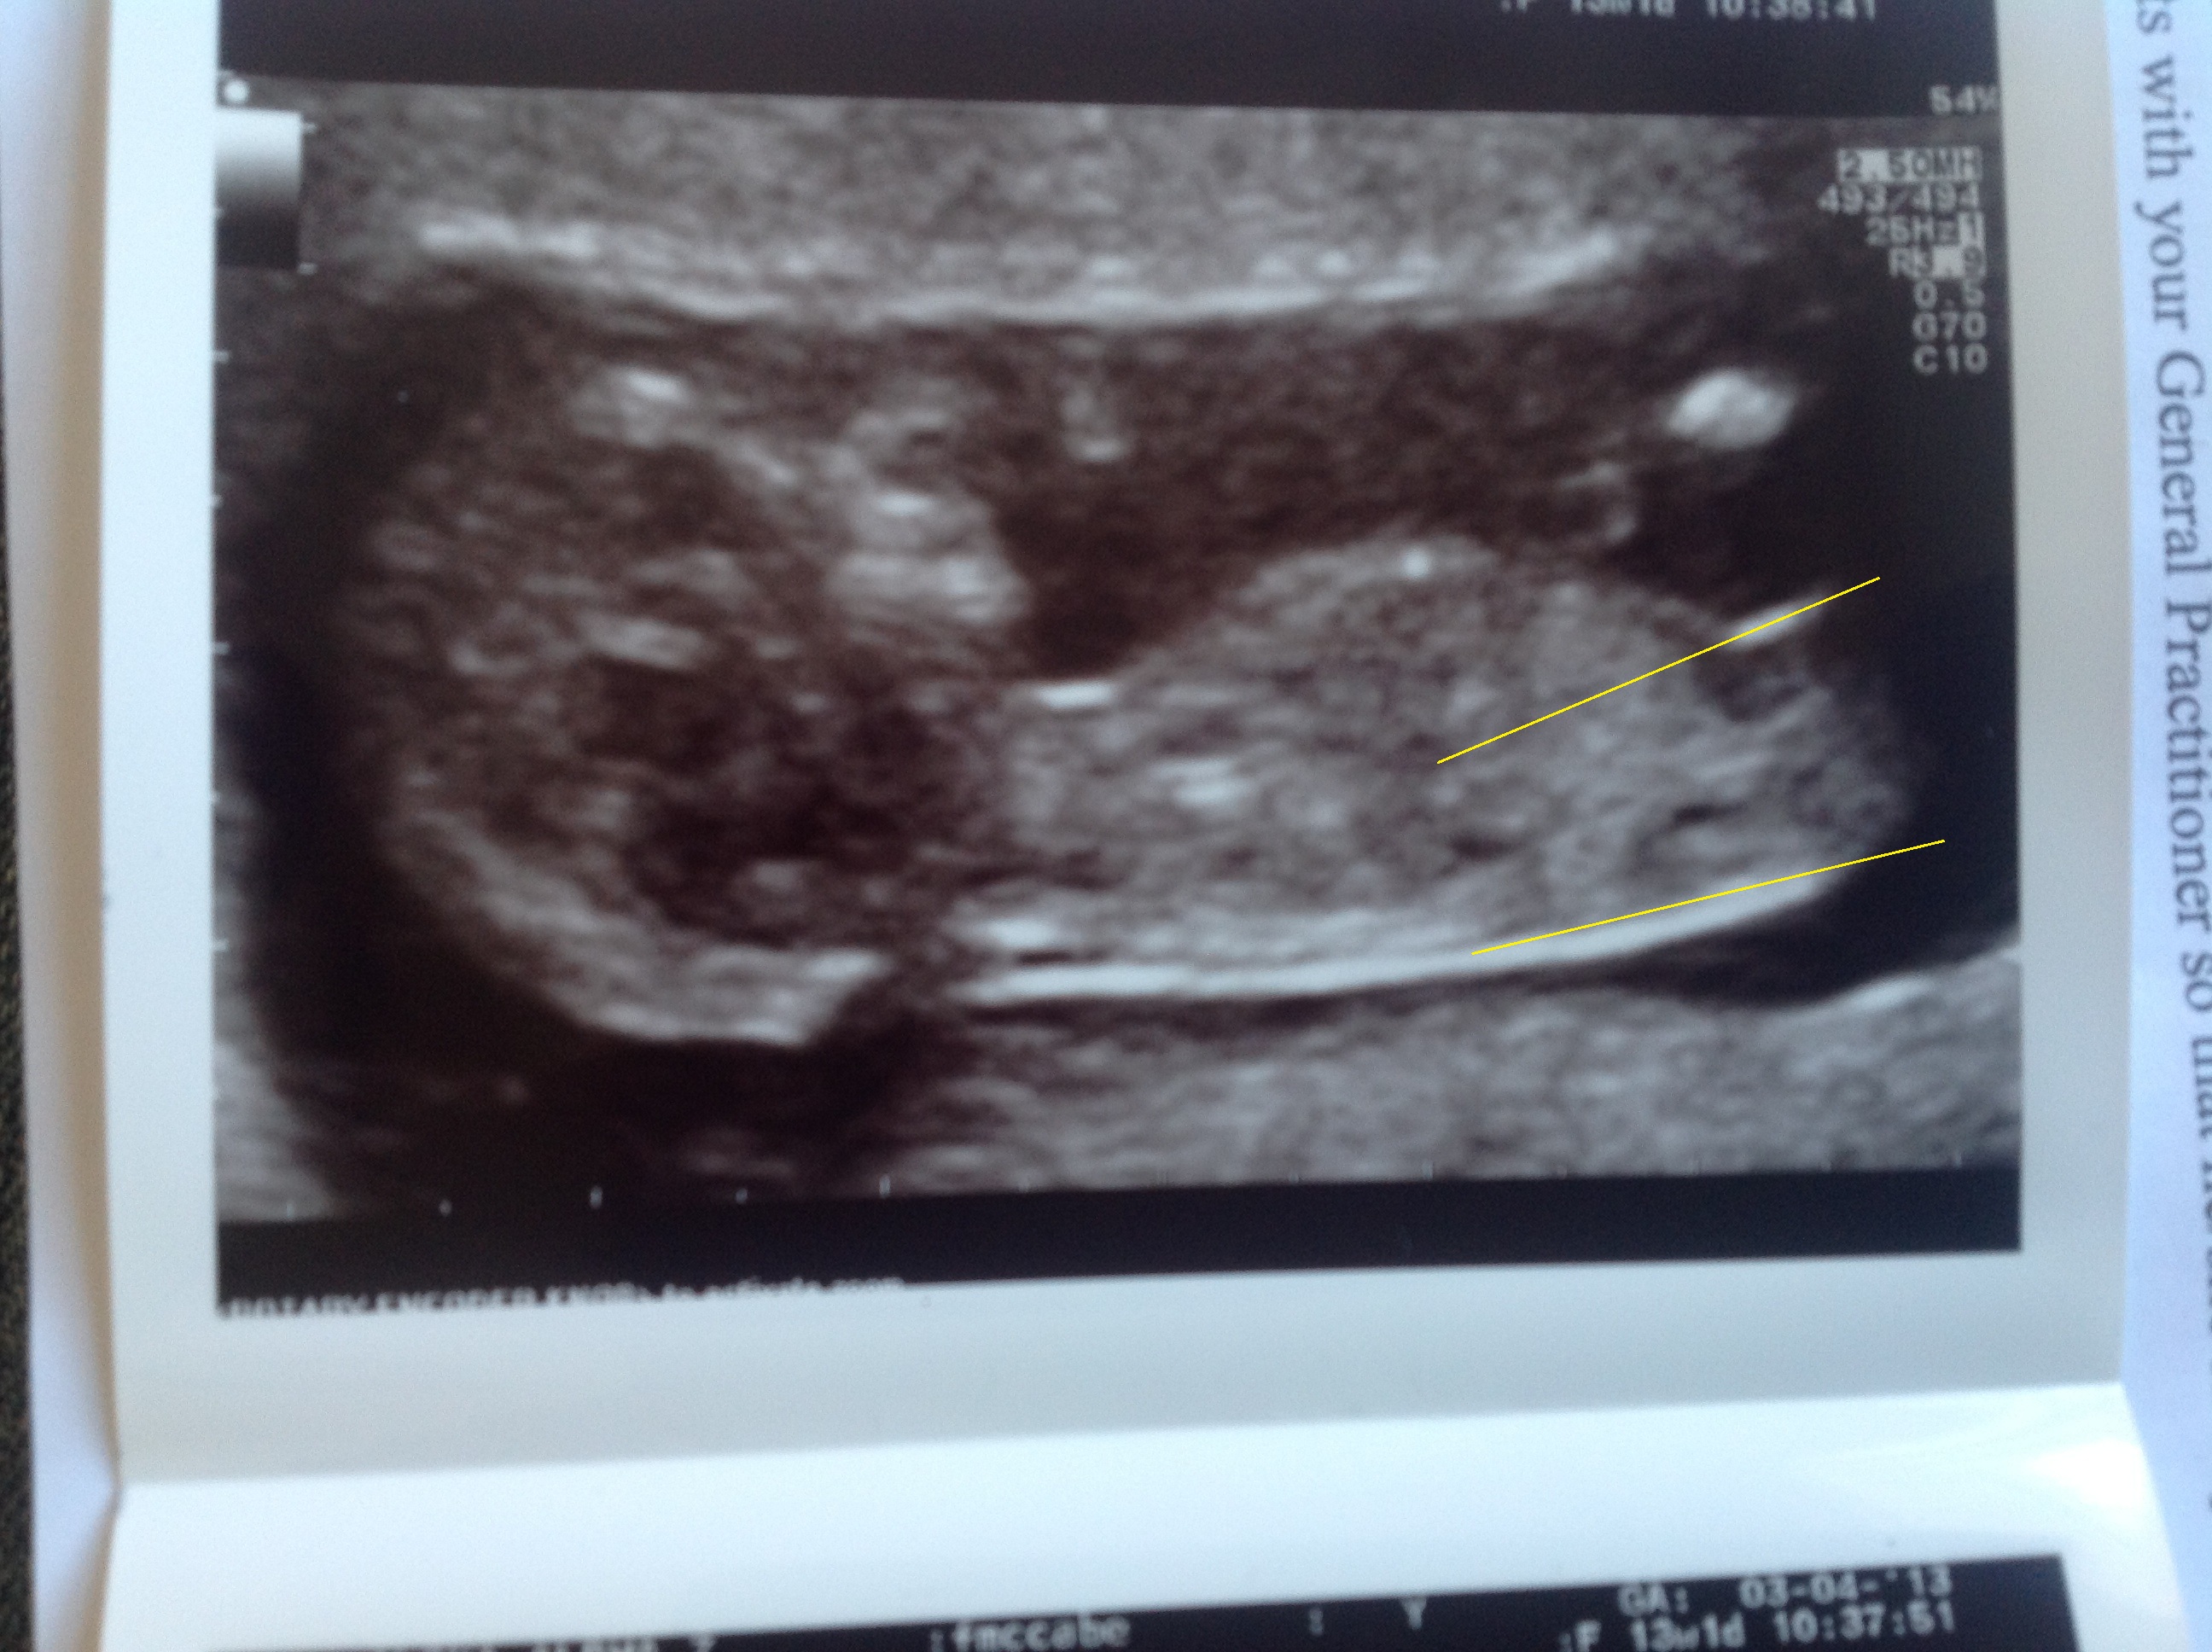

I have lines drew on, but am I right where I have them!!! I am starting to obsess now!!!

Attachment 10305

i think boy, but it'd be easier to guess without the lines in the way. i could see it going either way but i'm leaning boy right now, maybe the lines are throwing me off.

I would also like to see a pic without lines on it. I need to see if there's a bump on the nub or not. And.....do you have more pics?